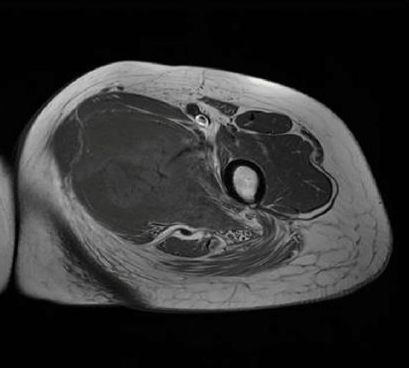

Magnetic resonance imaging (MRI) revealed a 4.7x7.2x9 cm irregular soft tissue mass in the left medial proximal thigh involving the adductor magnus muscle. The mass demonstrated intermediate and heterogeneous T2 signal intensity with an irregular peripheral T2 dark signal rim and intermediate T1 signal intensity. Additionally, the MRI showed extensive surrounding muscle and subcutaneous edema with a branch of the deep femoral artery coursing through the mass. Gadolinium-enhanced images revealed multilocular cystic areas surrounded by intense heterogeneous enhancement of the solid components. The mass demonstrated features concerning for malignancy [Figure 1, 2, 3, 4]. A fluorodeoxyglucose (F-18 FDG) PET scan demonstrated mildly hypermetabolic lymph nodes in the left inguinal region (suspected reactive) and a few small inflammatory nodules without FDG uptake in both lungs, but no evidence of distant metastasis [Figure 5].

FIGURE 1: Axial T1-weighted MR image Intermediate T1 signal intensity of the medial thigh mass involving the adductor magnus muscle

FIGURE 2: Axial T1-weighted fat-saturated gadolinium-enhanced image Multilocular cystic areas in central part of lesion surrounded by intense heterogeneous enhancement of the solid elements

FIGURE 3: Axial T2-weighted MR image  Mass appearing with intermediate and heterogeneous signals

FIGURE 4: Coronal T2-weighted MR image Mass in adductor compartment of thigh with intermediate and heterogeneous signals